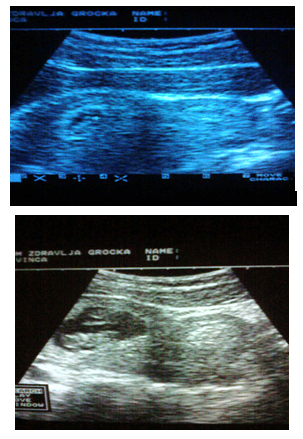

(Figures 1-3)

Figure 1 Patient D.M.1983.age1th pregnancy blighted ovum m.l.II.In next pregnancy ultrasound examinations were carried out 5time.A live female child was obtained by surgery1800/40.

Figure 2 Patient Dj.B.1983 age. Ultrasound examination carried out 5 times. Spontaneously delivered a live male child 2600/50.